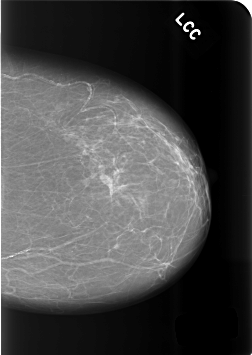

C_0485_1.LEFT_CC

LEFT_CC LINES 5680 PIXELS_PER_LINE 4024 BITS_PER_PIXEL 12 RESOLUTION 50 NON_OVERLAY